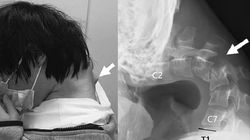

Szum uszny Dzień dobry, mam 30 lat jestem mężczyzną, od miesiąca męczy mnie szum uszny który wyraźnie nasila się w pozycji leżącej, w nocy i nad ranem, w ciągu dnia intensywność spada. Były nawet 3 dni, że zanikł zupełnie. Na początku po kilku dniach był nie do wytrzymania, potem osłabł w dzień a nasilił się w nocy. Nie stwierdził nic laryngolog (szereg badań również nasofiberoskopia), laryngolog, neurolog (tomografia), ortopeda na podstawie RTG również. Mimo wszystko podejrzewam przyczynę ortopedyczną ponieważ zaczęło się to w dniu kiedy mocno skręcając kark celem rozciągnięcia, ale wyjątkowo w ten sposób że trzymając głowę do przodu (nie przechylając na boki) obróciłem nią mocno w dwie strony i mocno chrupało. Jutro mam rezonans odcinka szyjnego, trochę się tego obawiam czy szumy się nie nasilą laryngolog powiedziała że czasem tak się zdarza. Szumy są na tyle silne, że nie pozwalają spać zwłaszcza nad ranem. Bardzo proszę o pomoc,

Przyjedź z płytą badań rtg i TK.